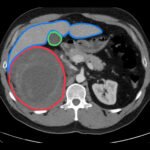

The authors present the case of a 42-year-old male who was evaluated in a community hospital emergency department (ED) with right upper quadrant and flank pain after falling onto his couch. His evaluation included computed tomography (CT) of his abdomen with intravenous contrast that identified a large right retroperitoneal hematoma measuring an impressive 17 centimeters (cm) in length. The patient was transferred to a receiving trauma center. Upon arrival a focused assessment with sonography in trauma (FAST) ultrasound was obtained. The interpretation of the findings was complicated by distortion of his anatomy by the hematoma. The patient remained hemodynamically stable and was admitted for continued observation. He was ultimately discharged home in stable condition. This case report provides a concise overview of the approach to evaluating blunt abdominal trauma, imaging considerations, and a brief review of the management of retroperitoneal hematomas.